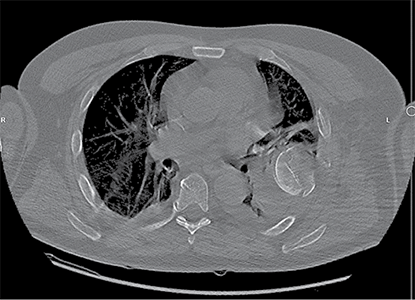

A 58-year-old patient was admitted to the Emergency Department of level I Trauma Center in August 2022 due to polytrauma sustained in a car accident. On arrival, the patient’s condition was severe, with decreased consciousness (GCS score of 12), unstable hemodynamic, subcompensated peripheral circulation, blood pressure of 62/32, and heart rate of 78 beats per minute. There was reduced breathing on the left side with a respiratory rate of 18 breaths per minute and an oxygen saturation (SpO2) of 85.0%. Palpation revealed pain in the left posterior chest. X-rays and CT scans were performed, which revealed a traumatic hemothorax on the left side, humeral head within the pleural cavity, three rib fractures, lung contusion, and hematoma.

Figure 1. First X-ray and computer tomography upon admission (with humeral head shown)